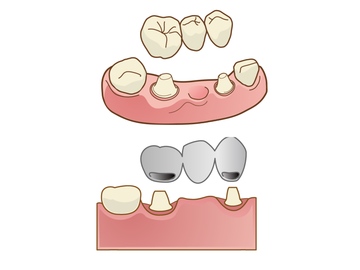

入れ歯の色々です。

部分入れ歯

保険適用

のは、留金の所が金属のものが多いです。

留金が金属じぁないもの(保険外)

全部総入れ歯

上のは、保険適用の入れ歯

です。保険外の総入れ歯

まとめ